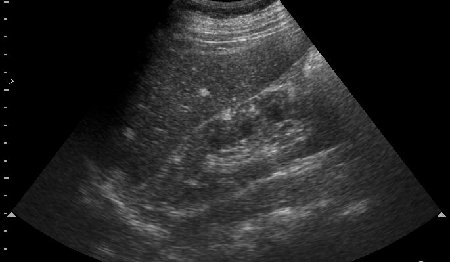

Парень 16 лет с эпилепсией. Изменения почек симметричные с обеих сторон. Ваши рекомендации?

УЗи почек - туберoзный склероз (болезнь Бурневиля)

В паренхиме поллиморфные гиперэхогеные очаги по типу ангиолипоматоза.Учитывая двустороннее поражение,да еще умственную отсталость,то возможна врожденная патология,которую Марио уже назвал( я бы остановилась просто на ангиолипоматозе

)

Все верно, туберoзный склероз. На сонограммах определяются образования типа ангиомиолипом/гемангиом почек/печени. Наличие судорог редполагает сходные изменения головного мозга - доказано на КТ.